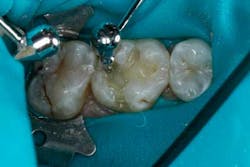

The depth of the cavity was determined to be 4 mm or less. The bulk-filled composite (Tetric EvoCeram® Bulk Fill) was placed in the preparation (Figs. 9 and 10). In this case, the first increment was placed, followed by additional material that was adapted to the tooth anatomy (Figs. 11 through 13). After further refining, the bulk-fill composite was light-cured in one increment for 10 seconds (1,200 mW/cm2).

The occlusion was checked and adjustments were completed (Figs. 14 through 16). After the final polish was accomplished, the restoration was completed (Figs. 17 through 19).